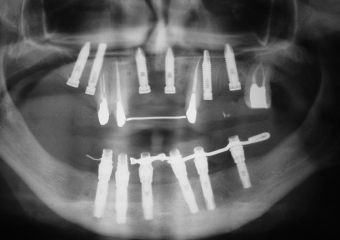

Imagem inicial em 2003 - Clínica Cliniface

Imagem inicial em 2003